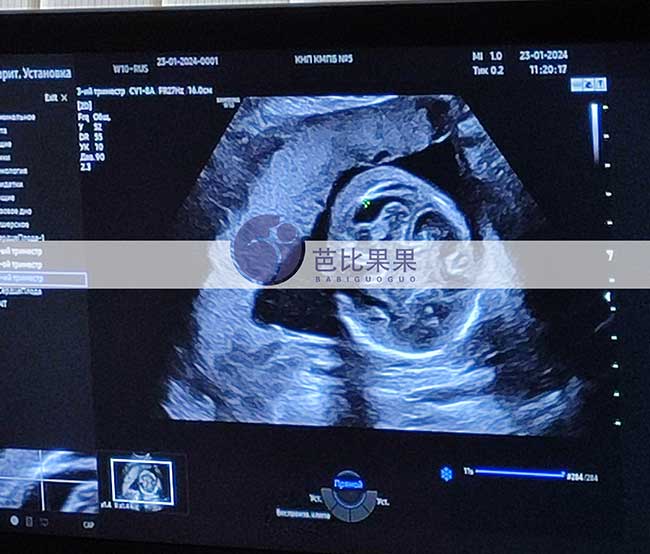

L先生在格鲁吉亚助孕的乌克兰试管妈妈到医院做四维彩超

格鲁吉亚客户L先生家的乌克兰试管妈妈到医院做四维彩超,检查顺利通关,胎宝宝的身体发育很好哦